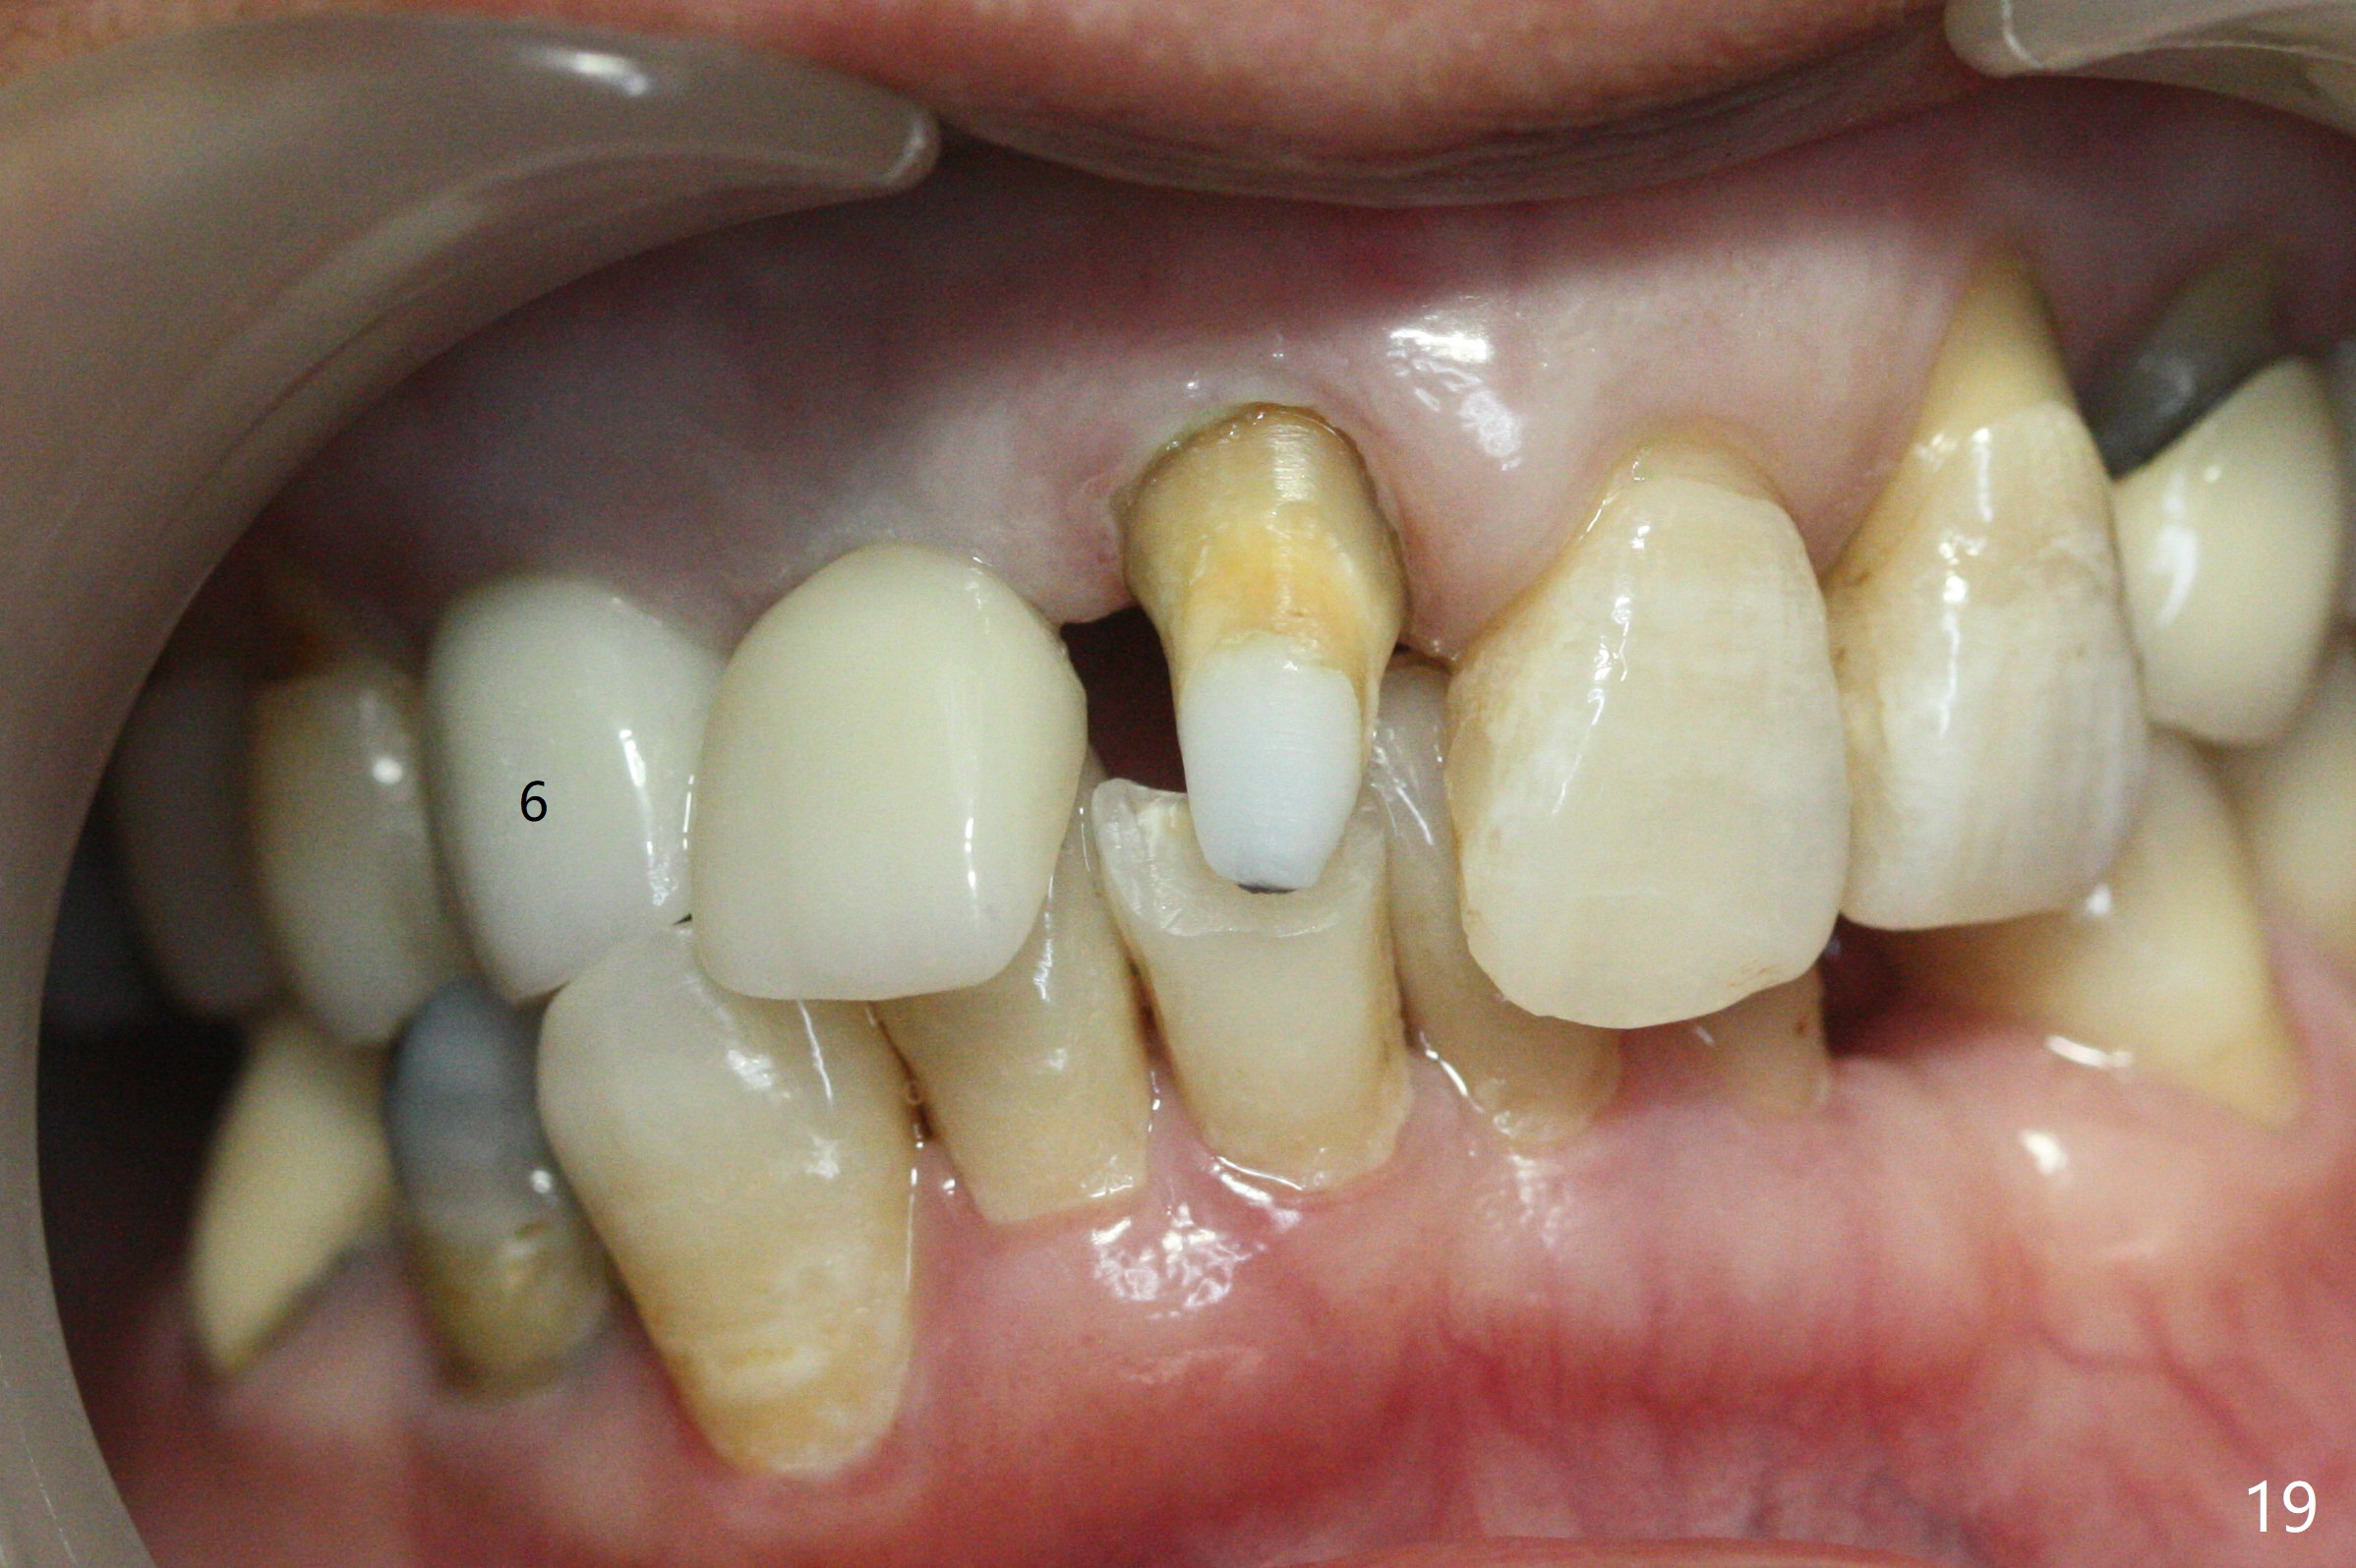

When the bridge is sectioned between #7 and 8, the tooth #6 is found non-salvageable (Fig.1). Incision shows the atrophic buccal plate at #7 (Fig.2 arrowheads); to prevent the same feature from happening at #6 with thin buccal plate, the most buccal portion of the root is preserved (socket shield (Fig.2-4: *)). The initial osteotomy is established in the palatal slope at #6 (Fig.5 circle) with 1.5 mm drill (Fig.6,7). A portion of the root is visible in Fig.6 (arrowheads). After sequential osteotomy with 2 mm, 3 mm (Fig.8) and 3.2 mm drills, a 4x15 mm implant is placed (Fig.10). To accommodate the cross bite, the coronal portion of the implant (Fig.9 white circle) is positioned close to the socket shield. It appears that the shield prevents the implant from encroaching the buccal plate.